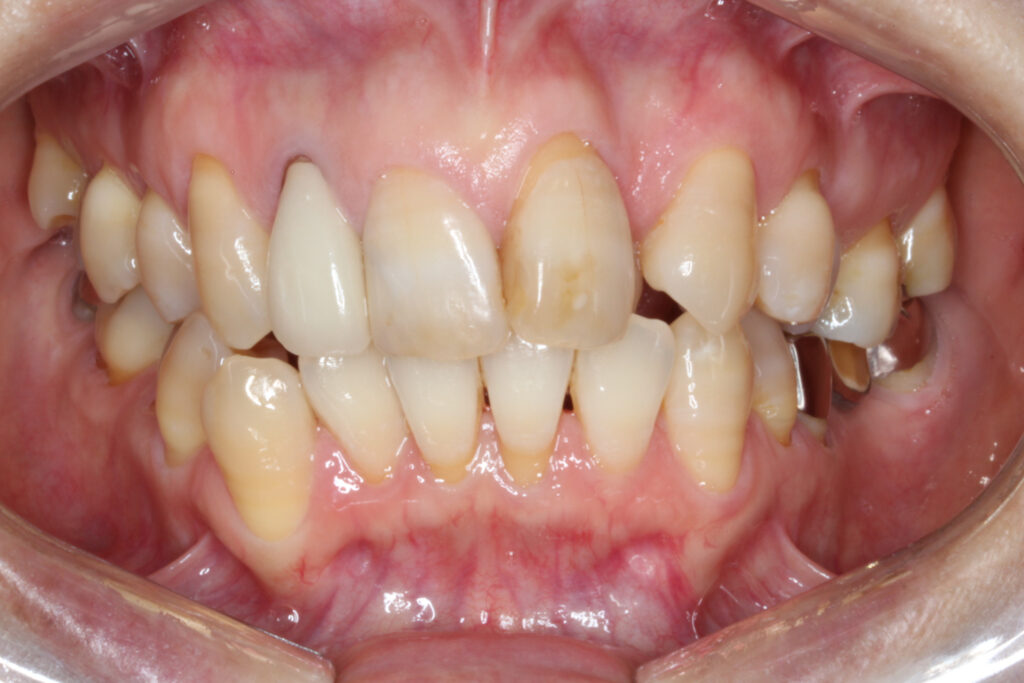

左上の前歯が内側に入ってしまっている(インビザライン)

左上の前歯が内側に入ってしまっているのが気になるということで矯正治療を行いました。

右上の2番目の前歯が完全に内側へ転位しており、1番目の前歯は大きく捻じれている状態です。

それに伴って上顎の歯並びの中心が左側へずれてしまっています。

また、下顎の前歯にもがたつきがあり、左下奥歯はブリッジが入っている状態です。

Before